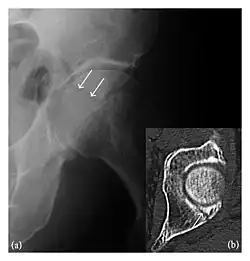

Occult osseous injuries may result from a direct blow to the bone by compressive forces of adjacent bones against one another or by traction forces during an avulsion injury. Lesions in the tibial plateau, hip, ankle, and wrist are often missed. In a tibial plateau fracture, any disruption of the posterior and anterior cortical rims of the plateau should be sought. Impaction of subchondral bone will appear as an increased sclerosis of the subchondral bone (Figure 1). In the hip, posterior acetabular fractures also present subtle radiographic findings. The acetabular lines should then be carefully examined keeping in mind that the posterior rim, which is harder to see on X-rays, is more frequently fractured than the anterior rim (Figure 2). In the wrist, detection of carpal bone fractures is often challenging, with up to 18% of scaphoid fractures radiographically occult. Carpal fractures, especially the scaphoid, are associated with the risk of avascular necrosis. In apparently normal wrist radiographs from symptomatic patients, if there is history of a fall on an outstretched hand with pain in the anatomic snuffbox, suggesting scaphoid injury, the initial examination with posteroanterior, lateral, and pronation oblique views must be complemented by other specific views such as supination oblique and the "scaphoid" view A careful examination of cortices for evidence of discontinuity or offset and cancellous bone for lucency is necessary (Figure 3).[1]

Figure 3: A 26-year-old man presenting with wrist pain after being assaulted. (a) Initial anteroposterior radiograph shows a subtle linear lucency within the scaphoid extending to the scaphocapitate articular surface that was overlooked (arrow). (b) Initial "scaphoid" view was negative. (c) Followup anteroposterior radiographs, 12 days later, shows obvious scaphoid fracture (arrows).[1]

Triquetral fracture usually occurs on the dorsal aspect by impingement from the ulnar styloid or avulsion of strong ligamentous attachment. The dorsal avulsion fracture or "chip fracture" appears as a small bony fragment on the dorsal aspect of the triquetrum and is best detected on the lateral view(Figure 4). When radiography is negative in patients with high suspicion of a fracture, both MRI and MDCT will be of value. However, it has been shown that MRI is superior for detecting trabecular fractures in carpal bones.

Figure 4: Dorsal triquetral fracture of the left wrist in a 30-year-old man after a trauma. (a) Anteroposterior radiograph shows a normal appearance. (b) Lateral radiograph of the same wrist demonstrates a chip fracture off the dorsal aspect of the triquetrum (arrow).[1]